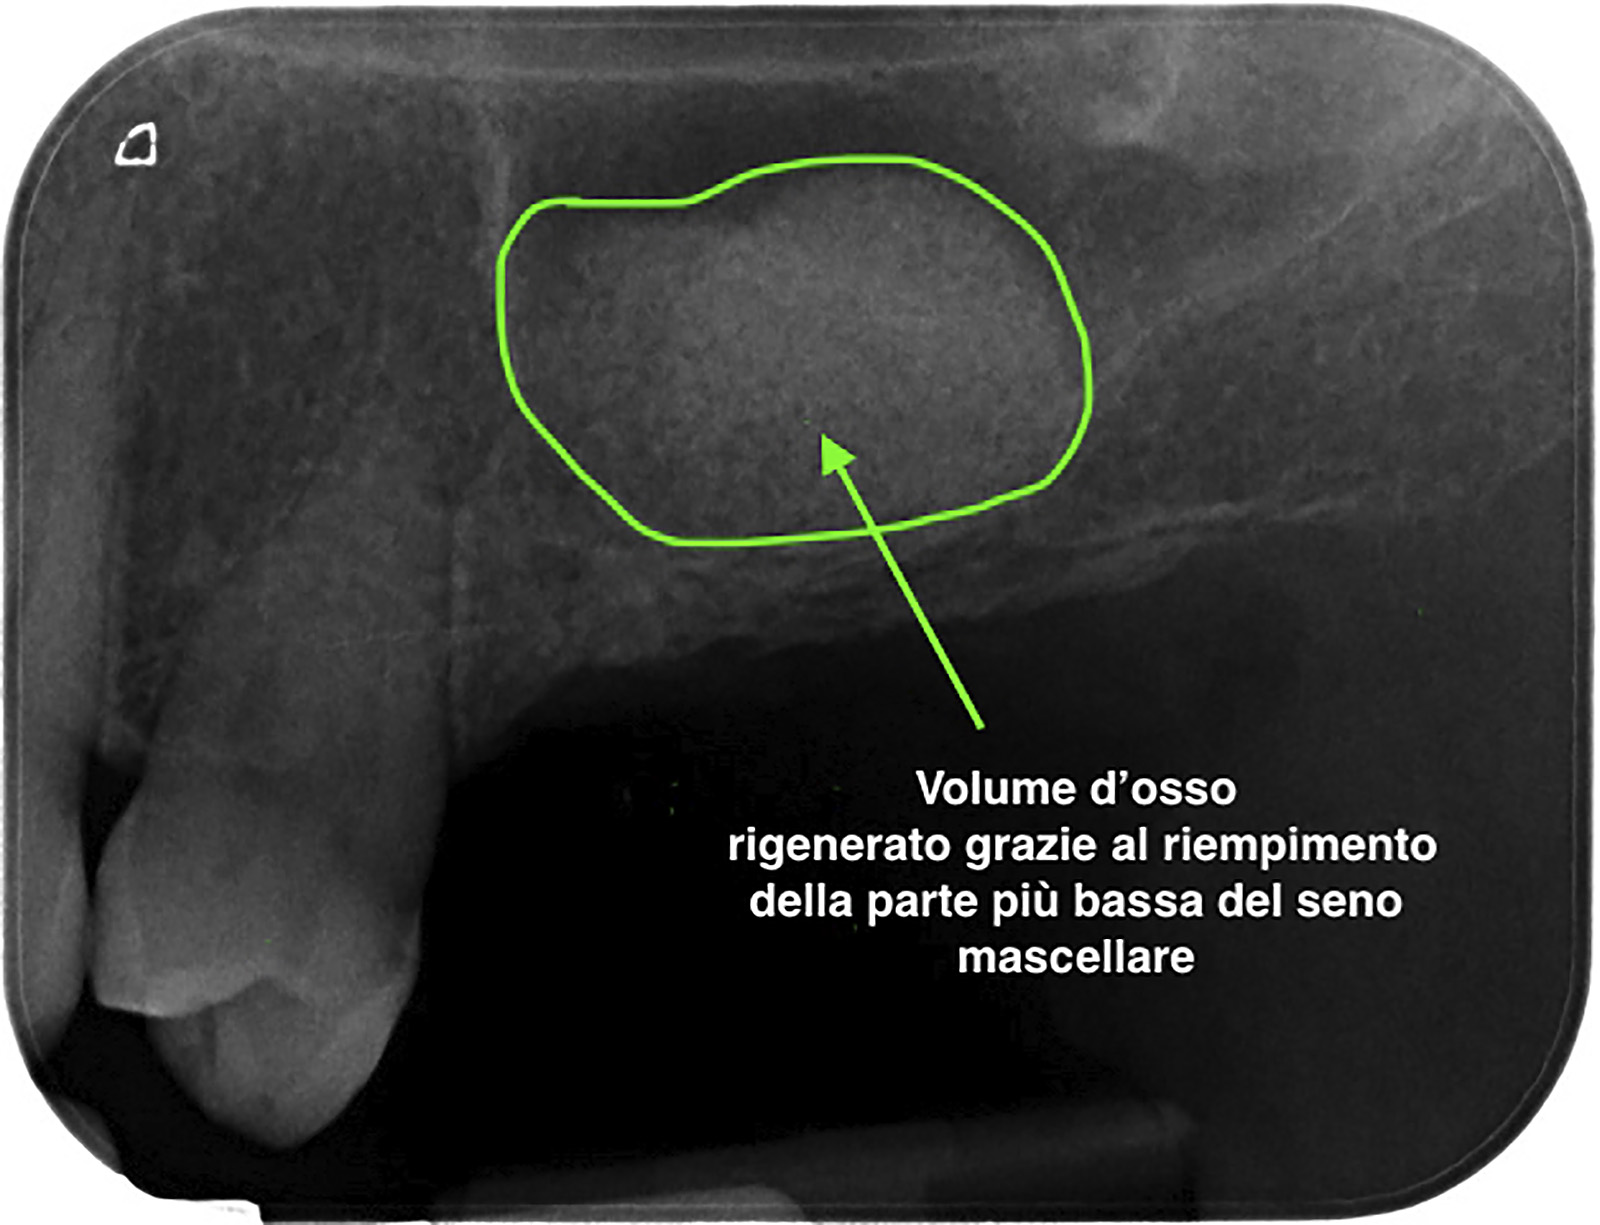

PREMESSA: in seguito all’estrazione dell’incisivo laterale superiore di destra, resasi necessaria per cause batteriche, si decide di affrontare il caso con il posizionamento di un impianto in sostituzione dell’elemento mancante dopo guarigione del sito infetto. Con tecniche rigenerative sia dei tessuti ossei mancanti a causa dell’infezione pregressa, sia dei tessuti gengivali che appaiono inizialmente troppo spostati in alto, si ripristina una corretta morfologia delle parabole (contorni) gengivali e delle papille interdentali (triangoli di gengiva tra due denti vicini).